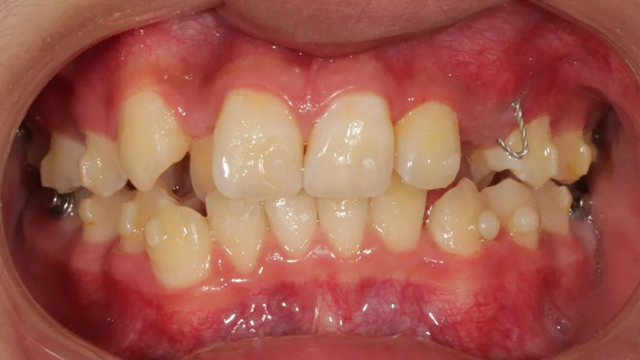

2021年8月(矫正前口内照)

这位小患者的口腔问题包括:牙列不齐,个别门牙反颌,左上尖牙完全埋伏阻生,另外,CBCT显示右上门牙牙根腭侧内还有一颗多生牙。

简单地说,牙齿不整齐只是小问题,他更大的问题是:在不该长牙的地方多长了一颗牙,而乳尖牙滞留,早该替换出来的尖牙长不出来,这两颗牙的问题如果不及时干预治疗,会带来很多长期的口腔问题。